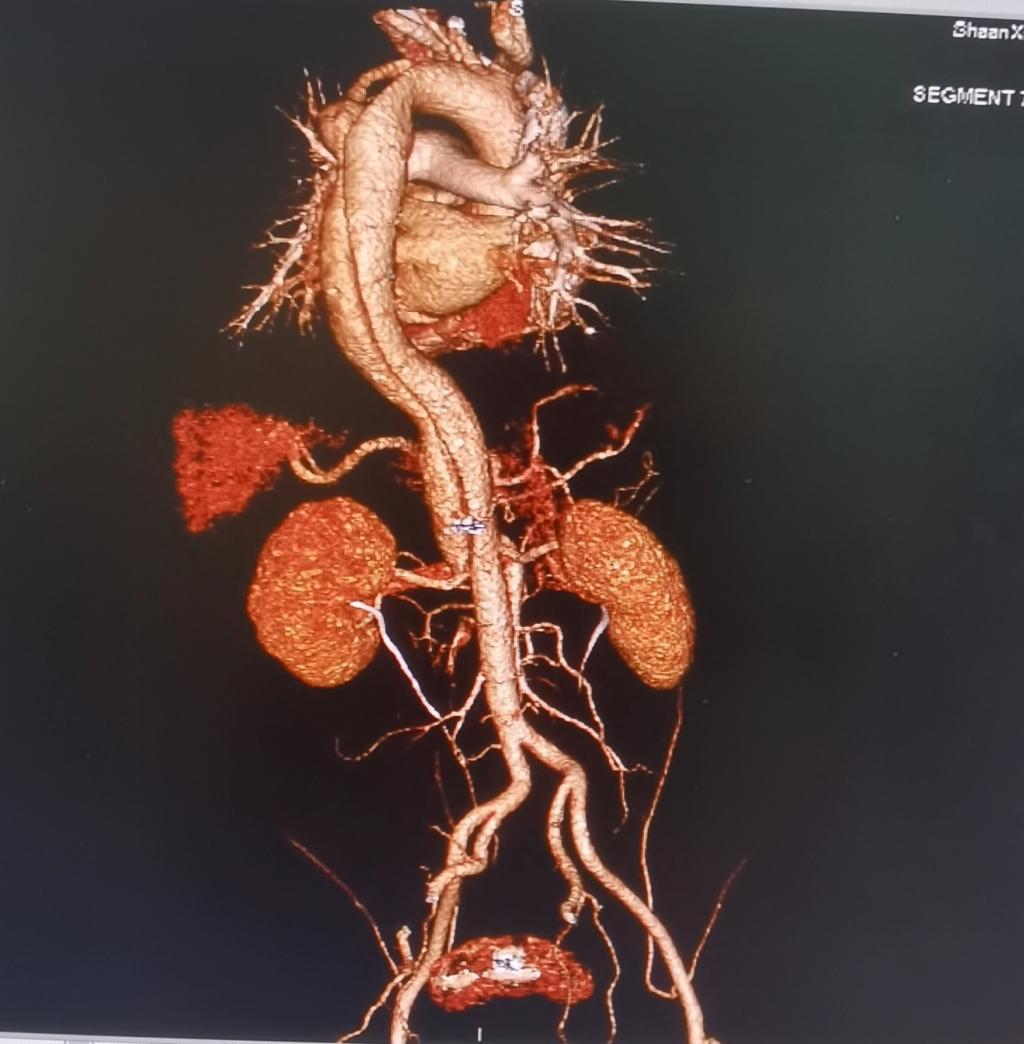

11月16日,王先生来渭南市健康管理中心进行一年一度的常规健康体检,当时无任何不适。当天下午16时40分,“中心”接到CT—MR影像科电话报危急值,王先生CT检查提示:疑似主动脉夹层,“中心”立即启动《危急值管理》流程,迅速处理。

17时20分,王先生来到医院,在“中心”张振华医师的全程陪同下在急诊科就诊。经胸心外科专家会诊,诊断为主动脉夹层(A型),并立即入院治疗。目前,该受检者已接受手术治疗,术后病情稳定。

主动脉夹层是一种非常凶险的疾病,其发病急、病死率高,如不能及时准确诊治,患者发病48小时内死亡率高达68.2%。此次健康管理中心快速反映、规范处置,与CT室,急诊科、胸心外科紧密配合,与死神赛跑,为该受检者在发现病情、及时救治,避免发生生命危险赢取宝贵时间。